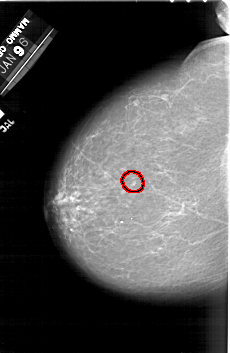

A_1492_1.LEFT_CC

LEFT_CC LINES 6346 PIXELS_PER_LINE 4126 BITS_PER_PIXEL 12 RESOLUTION 43.5 OVERLAY

FILE: A_1492_1.LEFT_CC.OVERLAY

TOTAL_ABNORMALITIES 1

ABNORMALITY 1

LESION_TYPE CALCIFICATION TYPE PUNCTATE DISTRIBUTION CLUSTERED

ASSESSMENT 4

SUBTLETY 3

PATHOLOGY BENIGN

TOTAL_OUTLINES 1